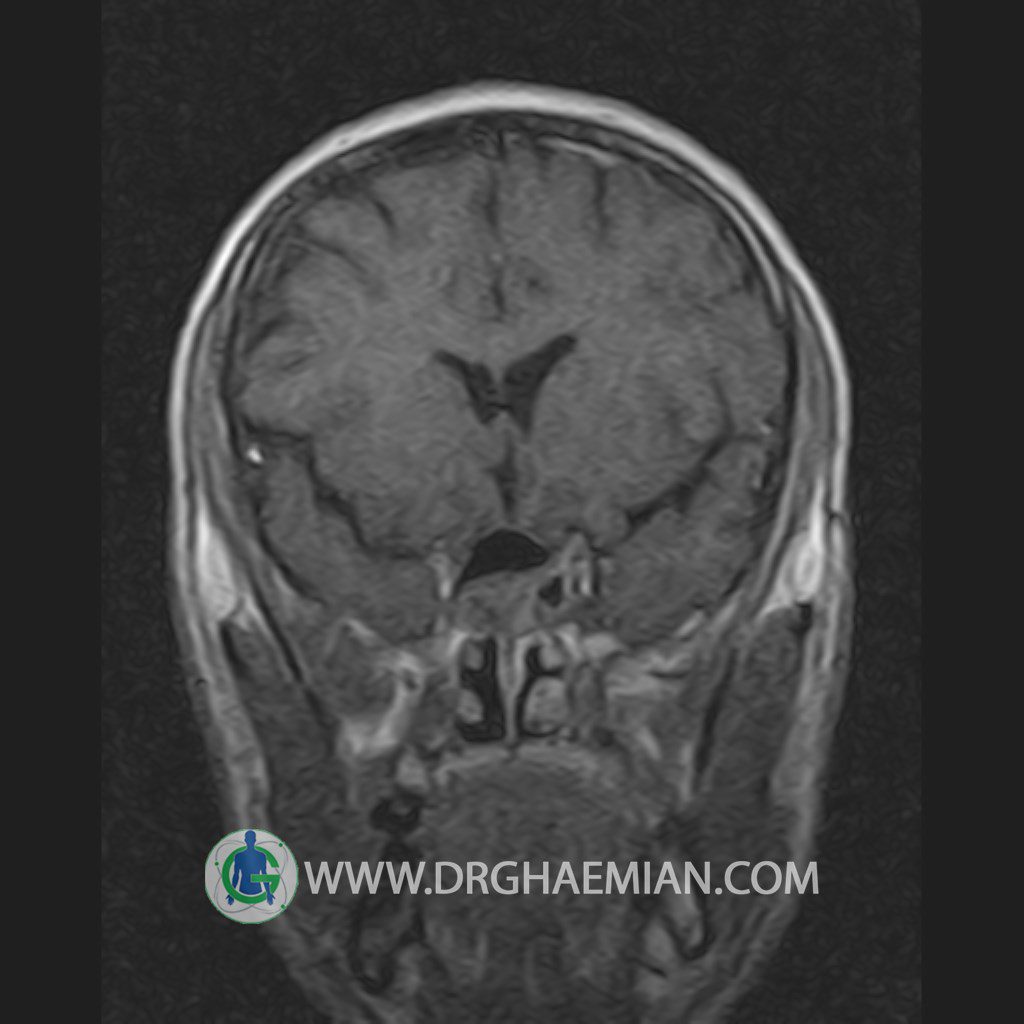

پزشکان اغلب از تصویربرداری ام آر آی برای تشخیص و درمان عارضه های پزشکی که فقط با استفاده از اشعه ایکس یا میدان مغناطیسی و امواج رادیویی قابل مشاهده است، استفاده می کنند. دستگاه ام آر آی تصاویر دقیق از ساختار های داخلی بدن ایجاد می کند. در این کیس یک میکروآدنوم در هیپوفیز بیمار مشاهده می شود.

HYPOPHYSIS MRI

(with and without contrast)

Technique: Axial , coronal T1 , Axial , coronal , sagittal T2 , Axial, coronal T1 post Gd & 64 dynamic thin coronal slices.

REPORT :

The infundibulum is centered and of normal size .

The optic chiasm and suprasellar spaces appear normal .

The cavernous sinus and imaged portions of the internal carotid artery and carotid siphon are unremarkable .

Evaluable portions of the neurocranium show no abnormalities .

The sphenoid sinus is clear and pneumatized .

Imaging of the hypothalamus after contrast medium administration was normal.

– Small hypoenhancing mass lesion ( 3 x 4 mm ) in posterior of pituitary stalk suggestive for micro adenoma

– Mucosal thickening in ethmoid & maxillary sinuses

is seen